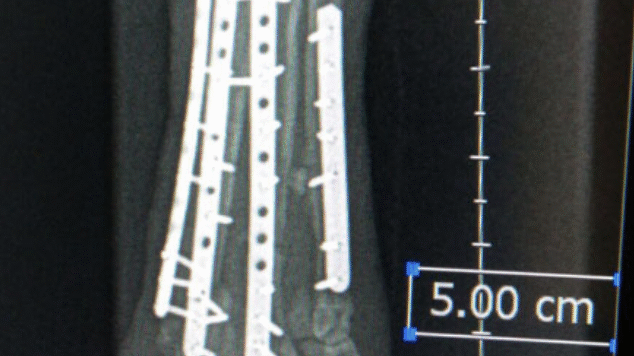

Metatarsal Plating

Example of metatarsal plating.